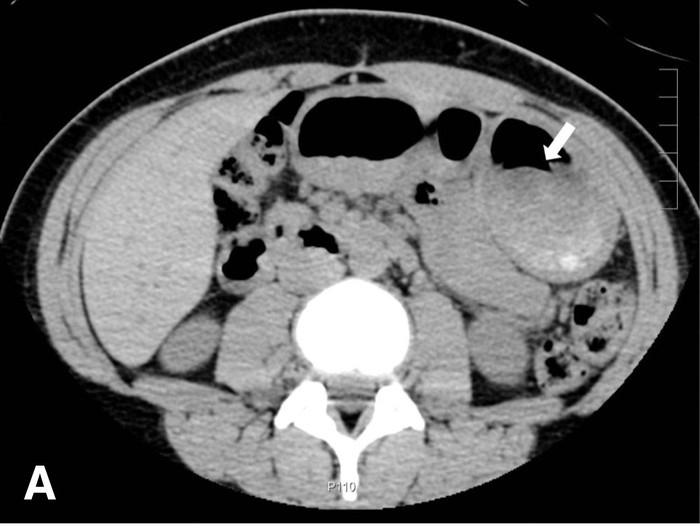

"Dalam kasus ini, kami tidak dapat mengidentifikasi benda asing kayu menggunakan pemeriksaan sinar-X polos, dan kami melewatkannya saat memeriksa tampilan aksial CT scan. Tetapi, kami dapat mengidentifikasi sendok kayu di lambung secara pasti saat kami menggunakan lebar jendela dan level jendela yang lebar untuk tampilan CT koronal," tulis para ahli yang dipublikasikan di The Journal of Emergency Medicine. (Foto: The Journal of Emergency Medicine.)